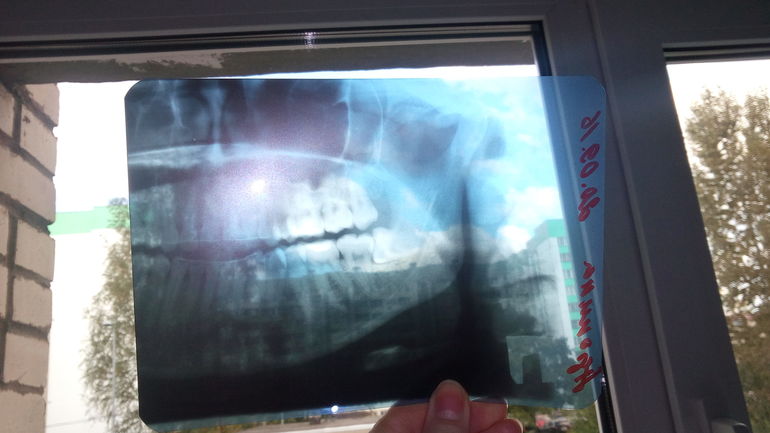

Девушки, кто сталкивался с удалением сложного нижнего ретинированного (прорезался только краешек) горизонтально расположенного зуба мудрости?

Долго ли, больно ли заживает? Особенно интересно, как оно после 30 лет...(говорят становится болезненнее тк зуб во всю развит уже).

Сегодня опять была у хирурга (воспалилась десна, щека, лимфоузел) сказал надо будет удалять, заживать будет примерно месяц, первые 2 недели на обезболивающем...страааашно ((((